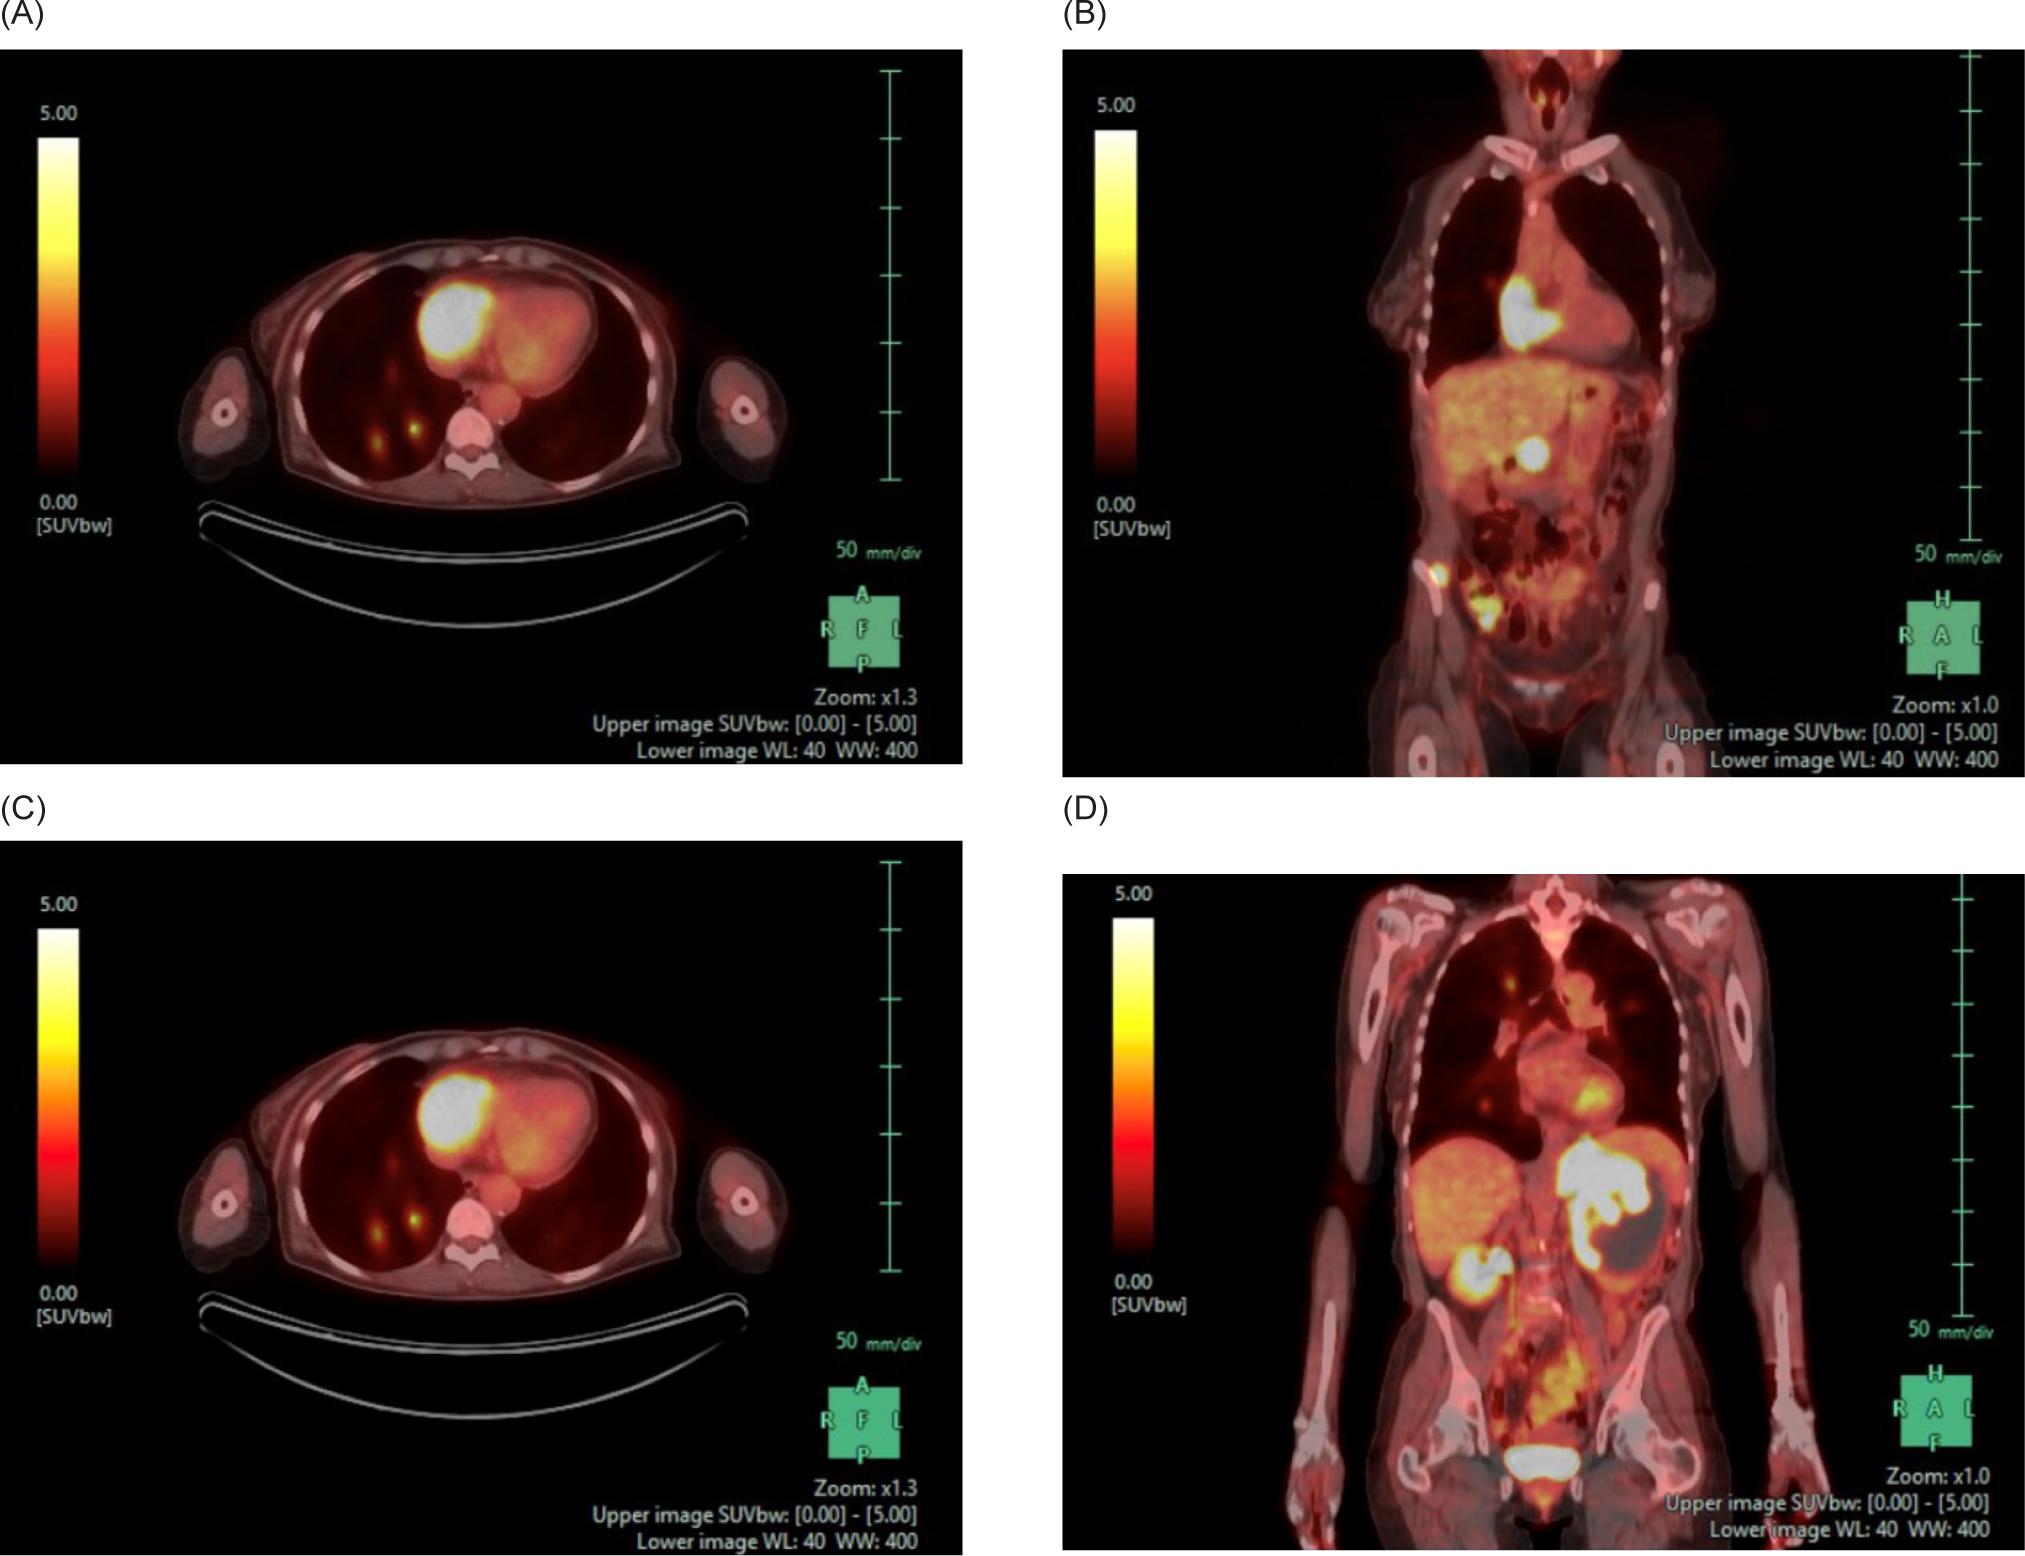

A 59-year-old female smoker with history of hypertension and hyperlipidemia who was screened for lung cancer with yearly low-dose CT scans was incidentally found to have a large left renal mass. Further evaluation via CT revealed a complex enhancing renal mass measuring 9.2.2 × 9.3 × 12.4 cm with extension into the left psoas muscle and abutting the pancreatic tail, spleen, and stomach (Figure 1). The patient underwent excision of a soft tissue mass, and surgical pathology was consistent with sarcoma. PET-CT scan revealed multiple avid lesions including lung nodules of up to 1.5 cm, a left adrenal mass, retroperitoneal adenopathy, and soft tissue metastases in the pelvic muscles as well as a lesion near the right atrium (Figure 2). An echocardiogram was performed in order to further evaluate the cardiac finding on the PET-CT scan, which revealed a 3.5 × 3.4 cm mass attached to the right atrial free wall, which was thought to represent a large thrombus or cardiac tumor, as well as a 0.75 cm mass noted on the atrial aspect of the IVC-RA junction likely representing the thrombus. Left ventricle ejection fraction was normal at 65%. The patient was instructed by her cardiologist to present to the Emergency Department for further evaluation given these findings. On presentation, the patient reported intermittent left flank pain, EKG was normal sinus rhythm with no acute ST changes, and CTA scan revealed likely invasion of perivascular nodules in the right upper lobe into subsegmental pulmonary arterial branches with associated pulmonary emboli within the distal subsegmental and more distal branches. The following day, cardiac MRI confirmed an intra-cardiac tumor occupying the entire right atrium with extension through the myocardium into the epicardial space and through the tricuspid valve into the right ventricle (Figure 3). MRI brain revealed three lesions consistent with metastatic disease. Renal biopsy was consistent with clear cell RCC with sarcomatoid features (Figure 4). Immunohistochemical studies were positive for desmin, PAX8, and myogenin, and negative for CK7. Patient was identified as poor risk per International Metastatic RCC Database Consortium (IMDC), with a median survival of 7.8 months. The patient received Ipilimumab and Nivolumab for one cycle, followed by Nivolumab only due to complication of diarrhea requiring steroid therapy. After three months of therapy that included three cycles of total therapy, she was noted to have partial response per Response Evaluation Criteria in Solid Tumors (RECIST) criteria. The patient will be continued on Nivolumab. The patient was also treated with gamma knife radiosurgery for her brain metastases.

Figure 2: PET-CT of the chest, abdomen, and pelvis. (A) Axial and (B) coronal views demonstrating a FDG uptake of the right atrium suggestive of a cardiac metastasis. There are also FDG avid pulmonary nodules. (C) Axial and (D) coronal views demonstrating a heterogeneously attenuating 9.6 × 8.7 cm left renal mass and accompanying 5.9 × 4.3 FDG avid adrenal mass. There is also a 2.6 × 1.2 cm FDG avid right adrenal metastasis and multiple FDG avid abdominopelvic nodules.